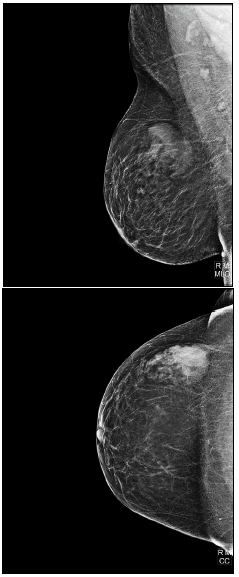

Paciente, 50 anos, com nódulo palpável em exame físico, comparece com resultado de mamografia. Observe as imagens a seguir:

A imagem demonstrada é característica de qual lesão?